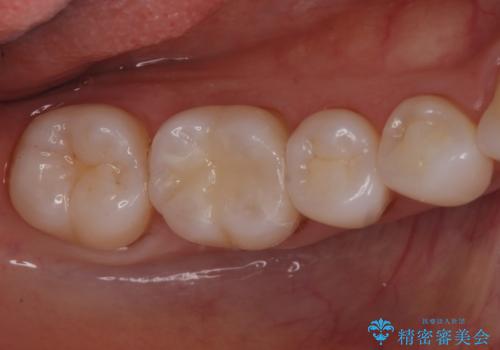

黒ずみもなくなり、虫歯も取り切ることができ大変満足していただけました。

虫歯の除去後に適合の良い修復物を装着することは今後の虫歯リスクを減らすことに繋がります。